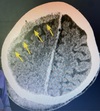

2

Metástases cerebrais Pontos hipertenso com edema perilesional